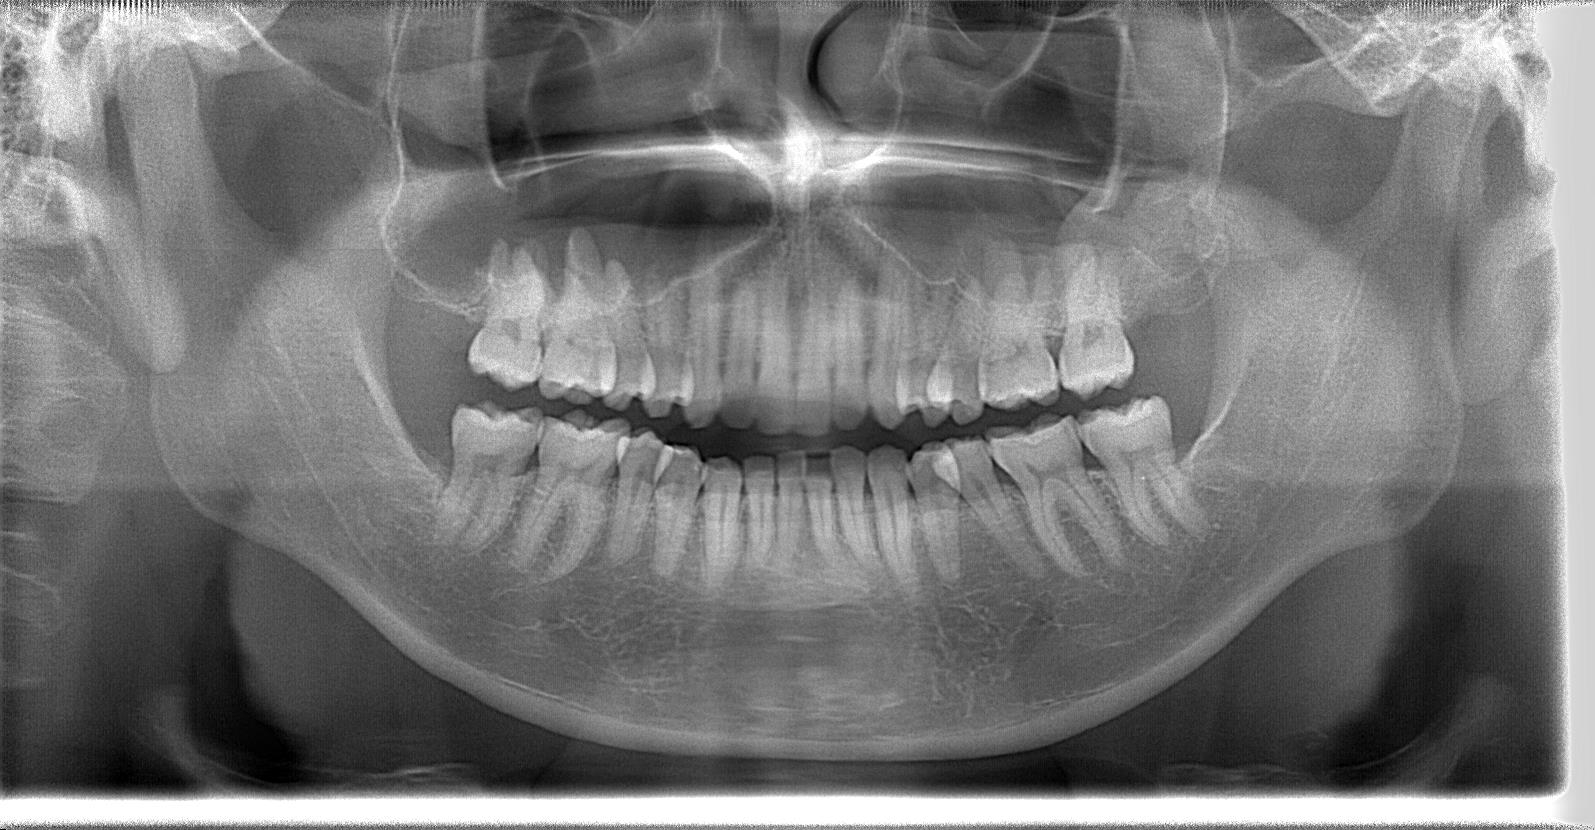

30代前半男性、8埋伏歯の抜歯症例

レントゲン写真の状態を御覧ください。

術後パノラマ写真